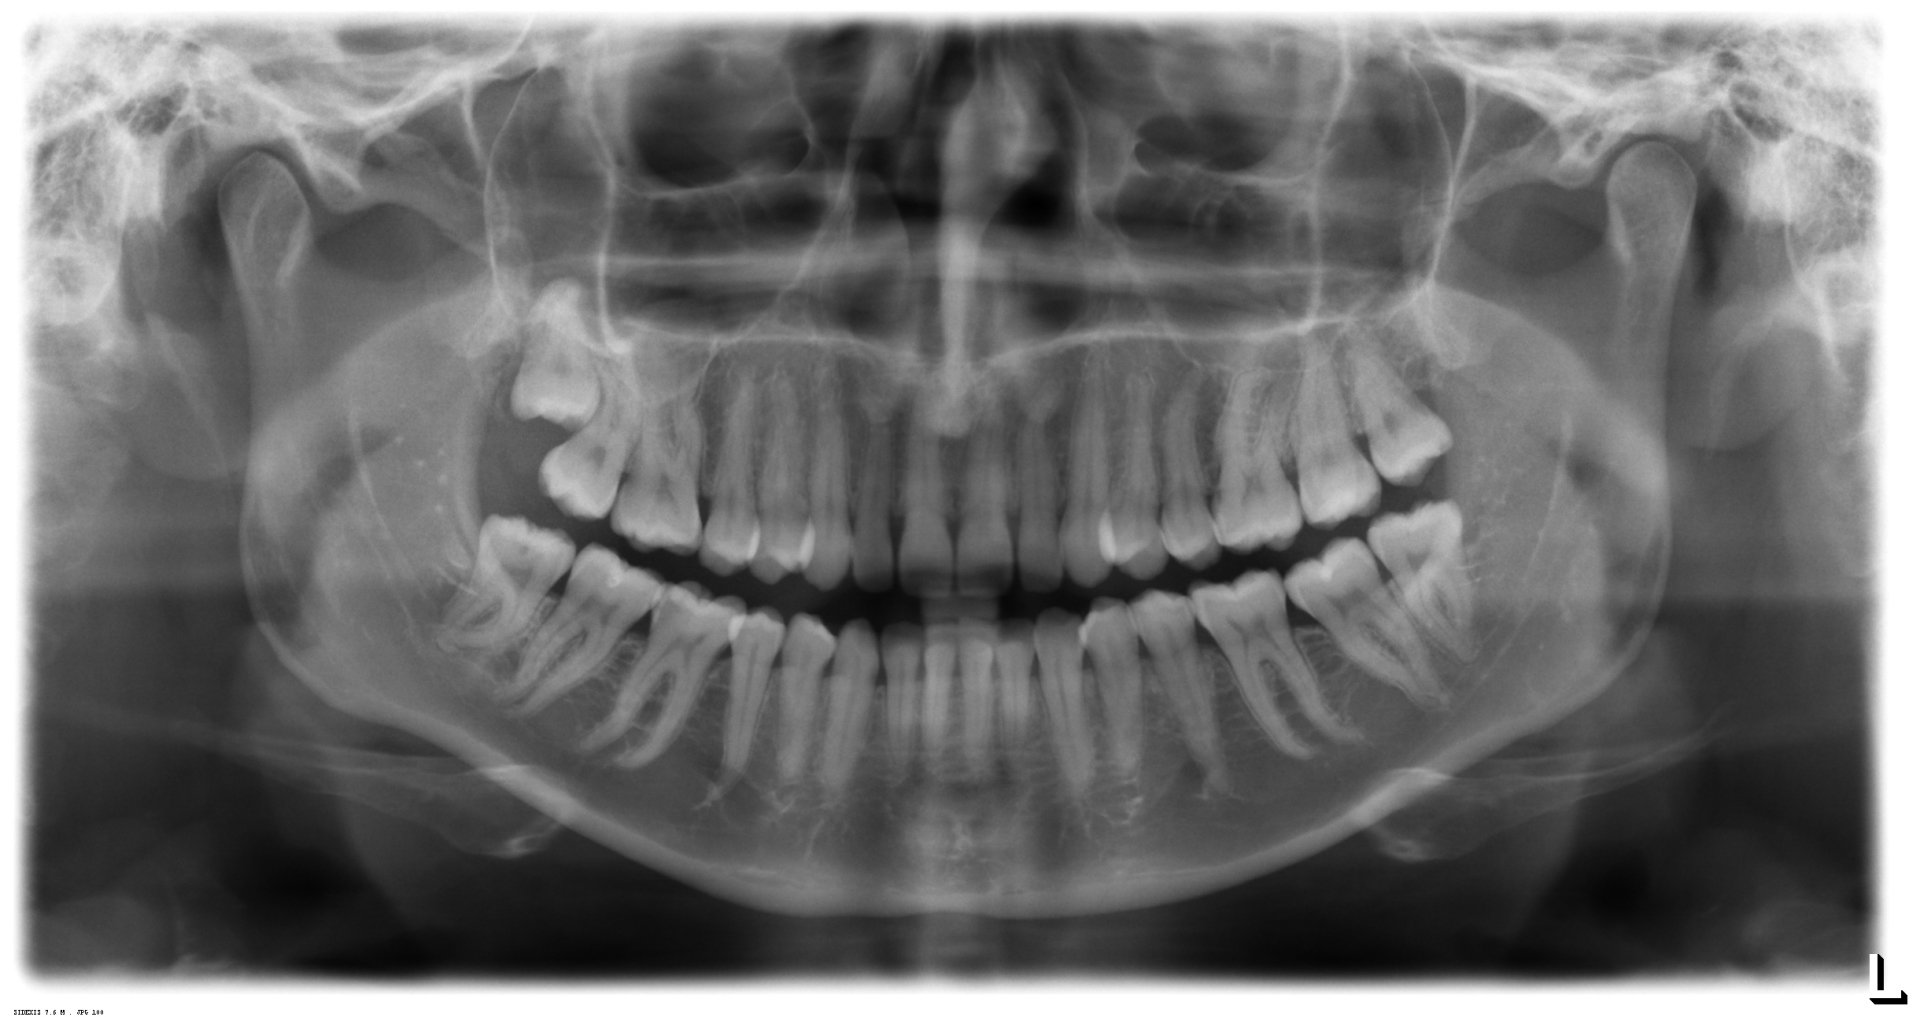

Wann sollten Weisheitszähne entfernt werden?

Zysten

Odontogene Zysten, Tumore

Wiederkehrende Entzündungen

Risiko: Lebensbedrohliche Entzündung

Karies (auch am Zahn davor)

Karies kann bei Weisheitszähnen schwer und nicht langfristig gut versorgt werden

Vor Dysgnathie

Die Osteotomie führt durch die Weisheitszahnregion